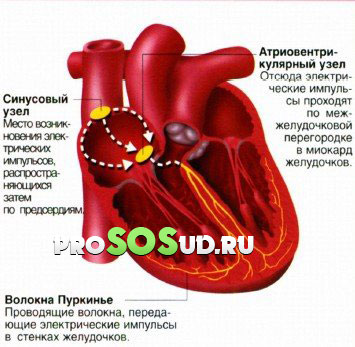

При диагностировании наджелудочковой пароксизмальной тахикардии контроль за сердечными сокращениями теряется из-за источника импульсов. Сигналы начинают поступать из «неправильного» очага автоматизма.

Этот очаг может находиться в предсердной или предсердно-желудочковой области. Проще говоря, патология локализуется выше желудочков сердца. Это первый механизм возникновения проблемы.

Второй механизм связан с циркуляцией импульса, который «движется» по замкнутому кругу. Такая циркуляция приводит к аномально высокому числу сердечных сокращений. Медицинские специалисты обозначили этот феномен как «повторный вход» возбуждения.

Данное состояние характерно для суправентрикулярной пароксизмальной тахикардии, возникающей из-за прохождения импульса «окольными» путями.

На самом деле, это целая категория заболеваний, которые проявляются нарушениями сердечного ритма. Причины этих проблем могут заключаться в синусовом или атриовентрикулярном узлах, а также в области предсердий. Мы уже упоминали о «обходных» путях. У наджелудочковой тахикардии существует своя классификация: